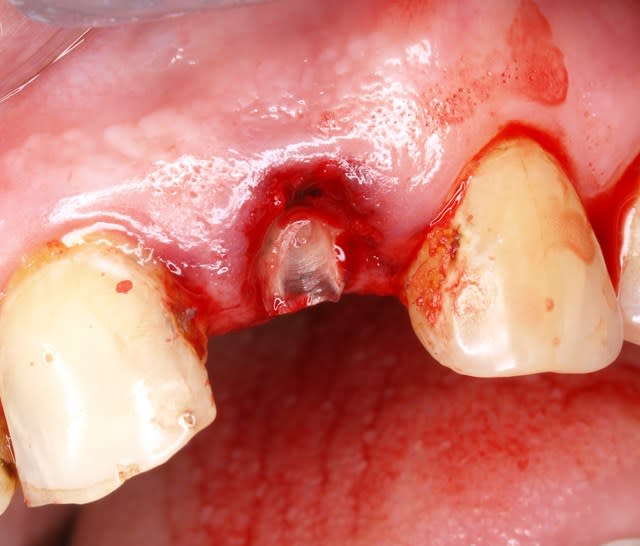

j enleve le ganulome je la remet .ca bouge a mort tant pis .

j attends 2mn sans bouger pour que le sang coagulé la cale un peu .

on est a des km des soucis de tarlouzes :le ligament comme ci comme ca ,contention deci dela , et precautions de on ne sait quoi.

et toujours pas d endo .meme pas un bisou a l apex

je la revois 1 semaine apres .

je prend une radio argentique .a ben ca alors on le voit bien mieux le canal.

gencive ras

douleur ras

mobilité grave .

on se revoit dans 3 semaine ok? ok !

et tjs pas d'endo pas de contention